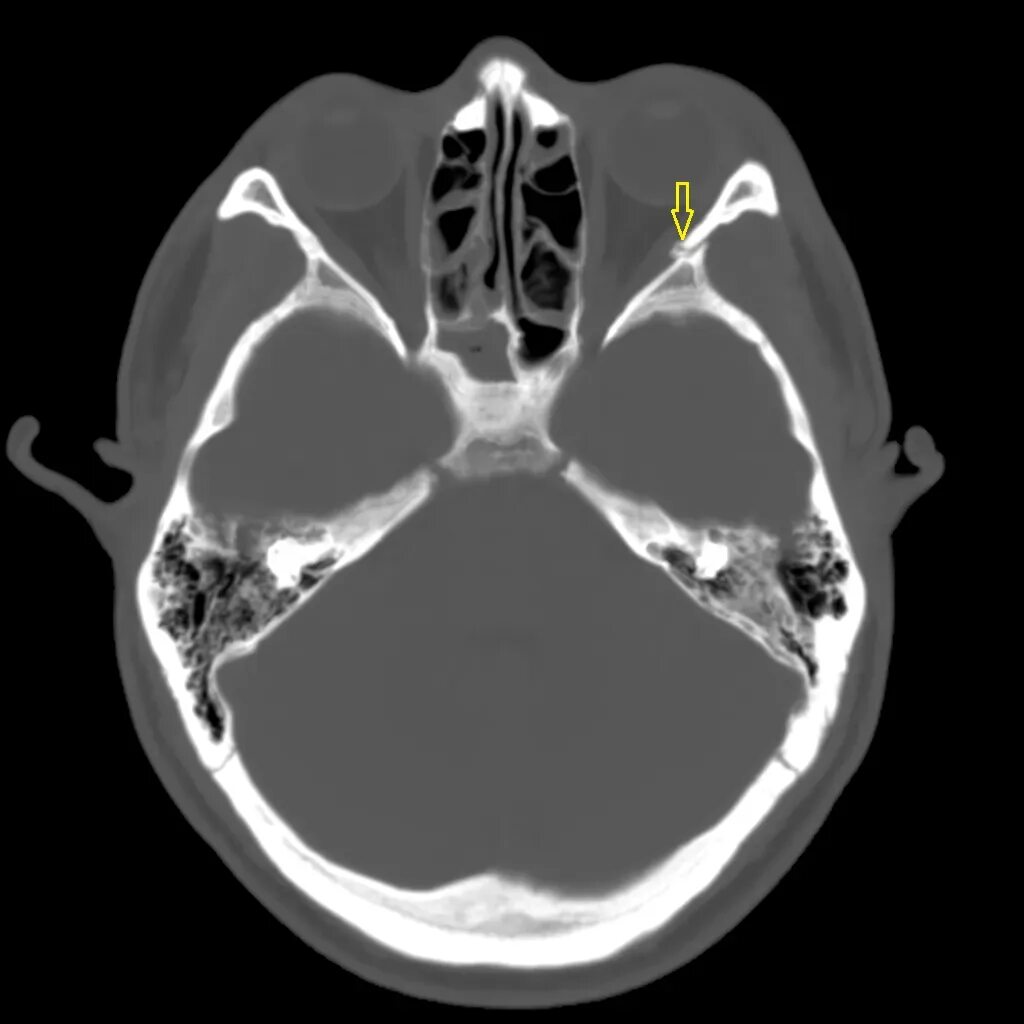

Череп на кт